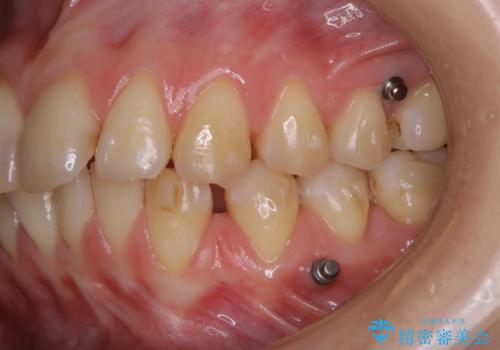

インビザラインでの治療中の患者様のクリーニング前後写真です。

- インビザライン矯正中に茶色が気になるとのことで来院されました。PMTC30分コースを行いました。

矯正治療中は虫歯や歯周病リスクが高くなります。